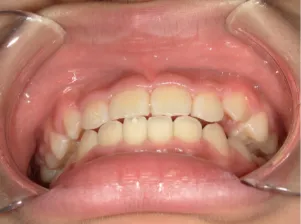

治療後⑧小6(12y3m):モノブロック装置継続中

治療後⑨中2(13y11m):モノブロック装置継続中

咬み合せも安定していて、口元の突出・口唇閉鎖不全も改善

*レントゲンや歯の萌出状況などから成長が終了していると考えられるため、現在残っている隙間や上下正中の不一致を改善するためマルチブラケット法へ移行するか検討中です。

治療は歯並びや口元などの状態から非抜歯治療で行う予定です。